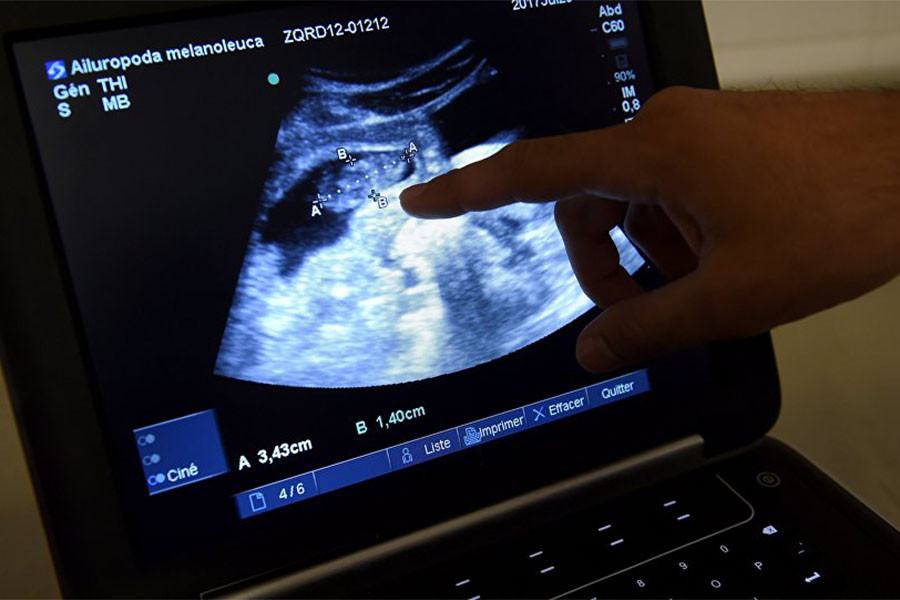

Slovakya, kürtaj olmayı düşünen kadınların operasyondan önce ultrason görüntülerini izlemesini hatta fetüsün kalp atışlarını dinlemesini zorunlu kılacak bir yasa tasarısını oylamaya sundu. Tasarı büyük tepki çekti.

Parlamentoda oylamaya sunulan tasarıya göre, kürtaj yaptırmayı düşünen kadınlar, ultrason görüntülerini görmeye zorlanacak. Bununla da kalmayan tasarı, ayrıca fetüsün kalp atışlarının dinletilmesini de zorunlu kılıyor.